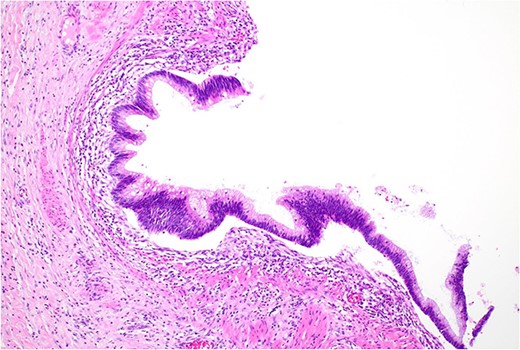

Histopathology macroscopically identified a 42-mm cystic caecal mass adjacent to the ileocaecal valve (Figs 4–5). Microscopic examination revealed a duplication cyst involving the ileal and colonic tissue comprised of a complete duplication of the colonic wall including mucosa, submucosa and muscularis propria, which was shared with the involved colon (Fig. 6). There was no mucosal connection to adjacent normal bowel. There was some ulceration with inflammatory changes in the overlying mucosa suggestive of prior cyst perforation and areas of attenuated villiform mucinous epithelium with features of low grade dysplasia (Figs 7-8). Special stains for organisms (Periodic Acid-Schiff (PAS), Fredericamycin A (FMA), Ziehl-Neelsen (ZN) and modified ZN) were negative. There were no granulomas, heterotopic mucosa or evidence of malignancy. Twenty-nine lymph nodes were identified with no evidence of malignancy.

Low grade dysplasia in duplication cyst epithelium, high power.